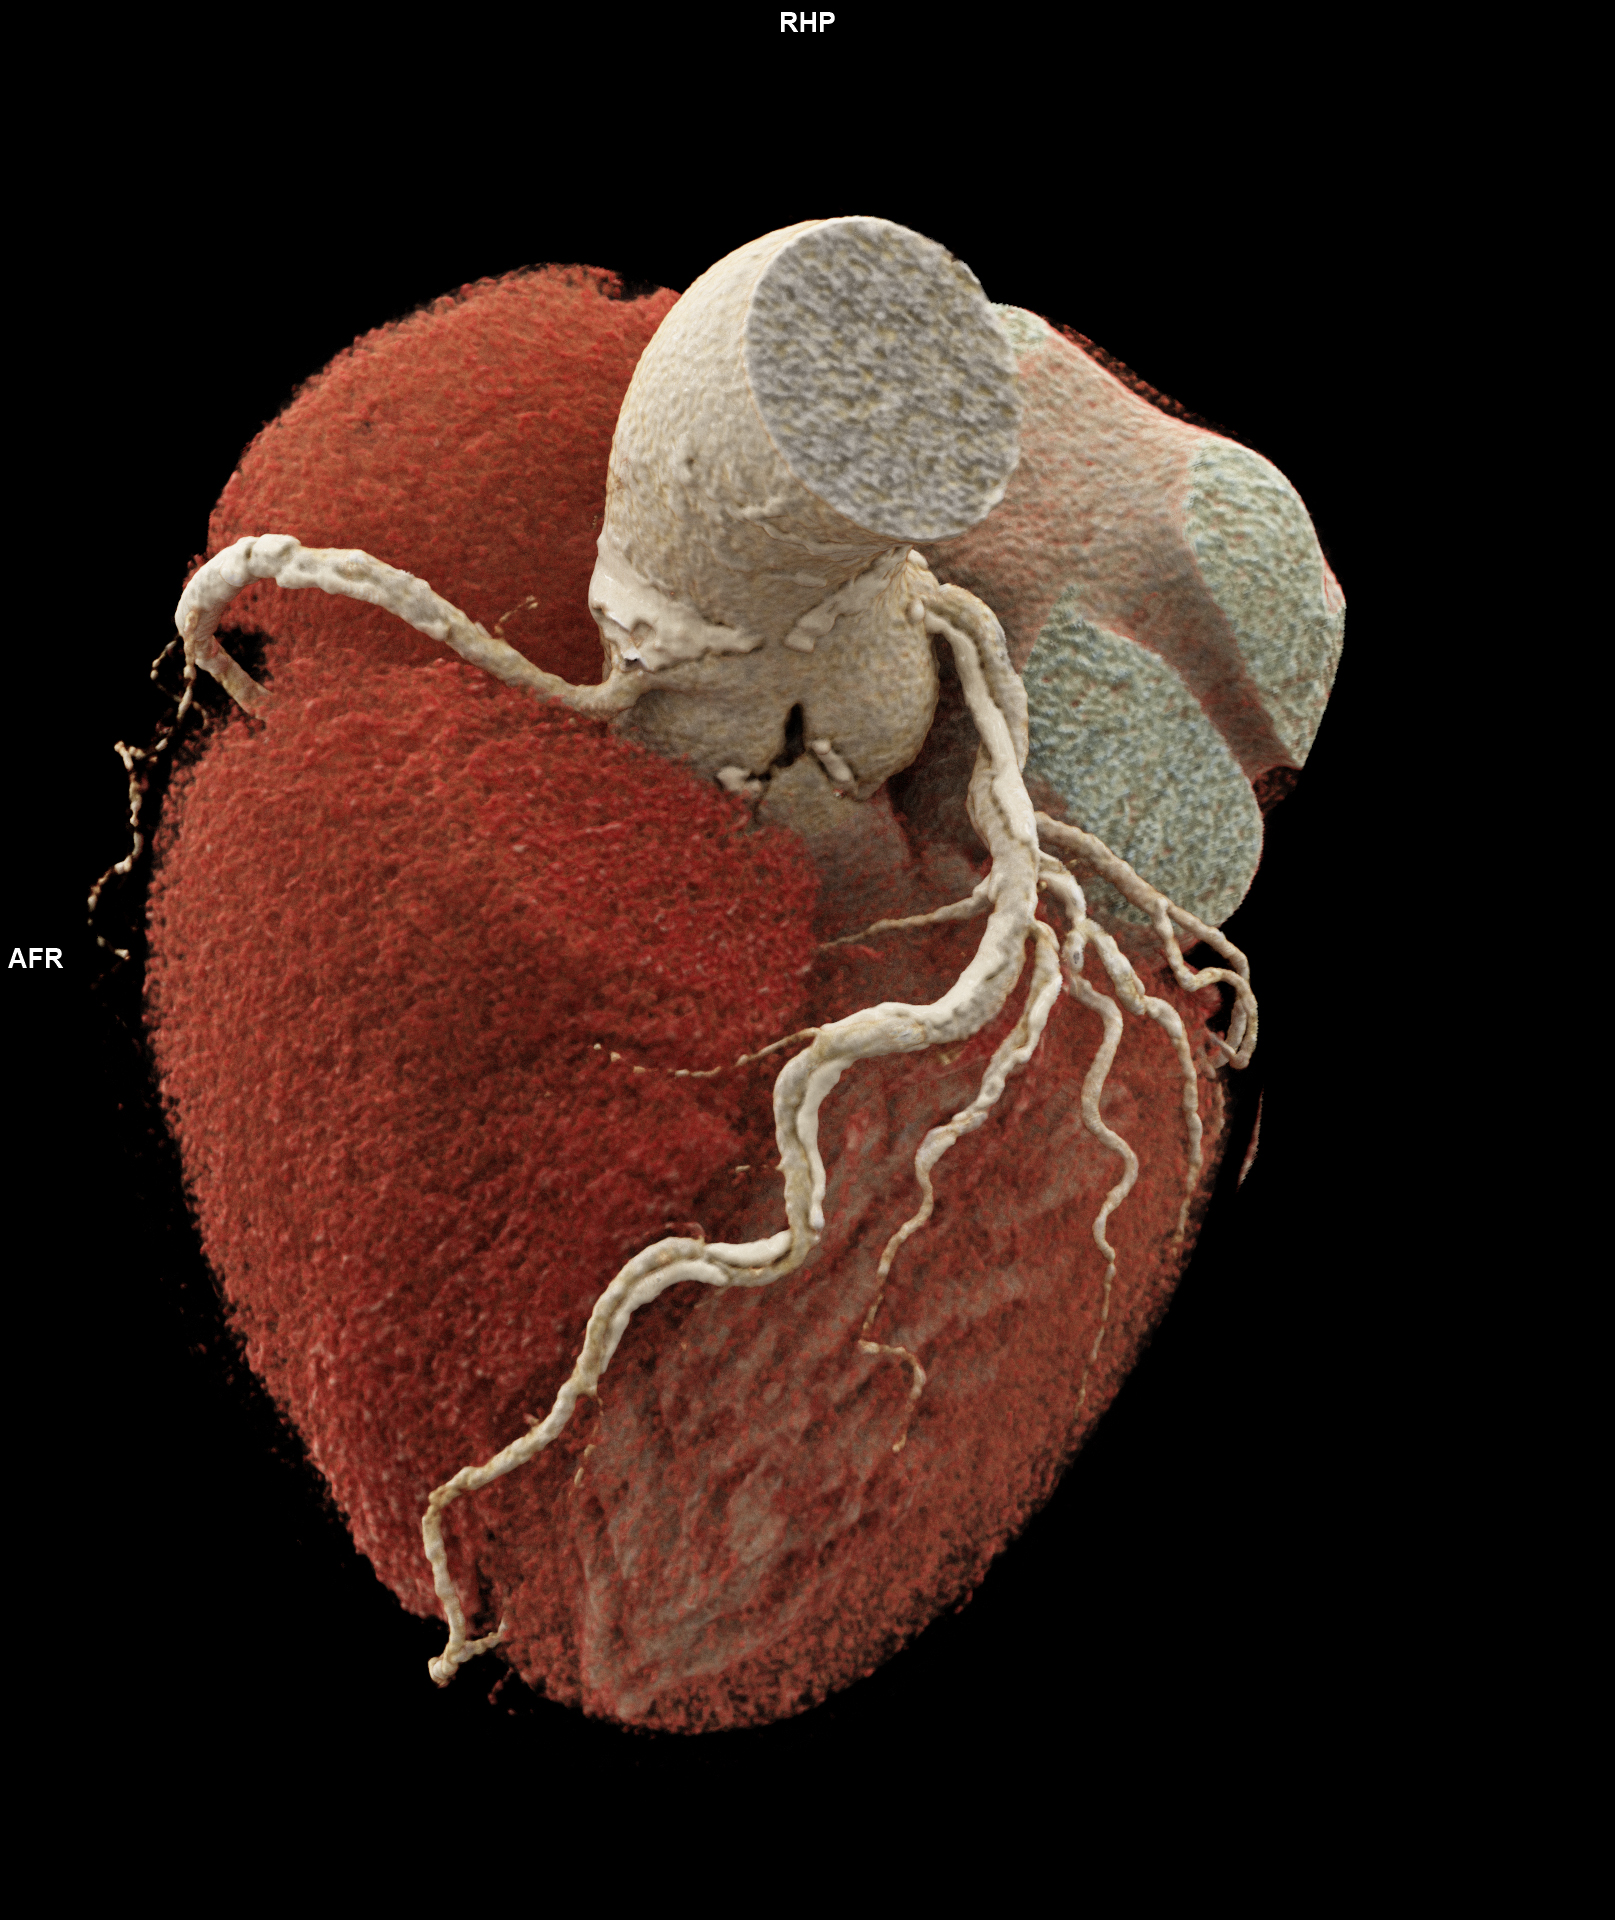

Die koronare CT-Angiographie eignet sich besonders gut zum Ausschluss einer koronaren Herzerkrankung bei Patient*innen mit niedrigem oder mittlerem Risiko für Veränderungen der Herzkranzgefäße. Bei Personen mit hohem Risiko gestaltete sich dies bislang aufgrund von häufig auftretenden koronaren Verkalkungen und Stents jedoch schwierig. Muhammad Taha Hagar, Erstautor der Studie und Arzt der Klinik für Diagnostische und Interventionelle Radiologie am Universitätsklinikum Freiburg erklärt: „In klassischen CT-Bildern erscheinen Verkalkungen der Herzkranzgefäße oft größer als sie tatsächlich sind. Dieser Effekt ist umso stärker, je größer die Verkalkung ist.“ Dadurch konnte es bislang zu einer Überbewertung von Verengungen und Plaques und in der Folge zu einer Überbehandlung kommen. Darum wurden diese Personen bislang schnell in den Herzkatheter überweisen oder in der Magnetresonanztomografie untersucht.

In der von Hagar und Kolleg*innen durchgeführten Studie wurden 68 Proband*innen mittels Photon-Counting-CT und einer invasiven Koronarangiografie als Referenzstandard untersucht. Die Patient*innen litten alle unter einer schweren Aortenklappenstenose, einer gängigen, aber ernsthaften Herzerkrankung, die den Blutfluss vom Herzen zur Aorta reduziert oder blockiert. Die Photon-Counting-CT-Untersuchung zeigte sich sehr genau in der Erkennung oder dem Ausschluss der koronaren Herzerkrankung. Auch wurde die Bildqualität in fast 80 Prozent als gut oder hervorragend bewertet.

Beim „Photon-Counting“ entsteht durch die hochauflösende direkte Umwandlung der eintreffenden Photonen ein digitales Signal, welches direkt auswertbar ist. Die Methode gilt damit als Grundlage für eine substantiell verbesserte digitale Patientenversorgung und für eine Nutzung der generierten Daten für zukünftige Therapieansätze.